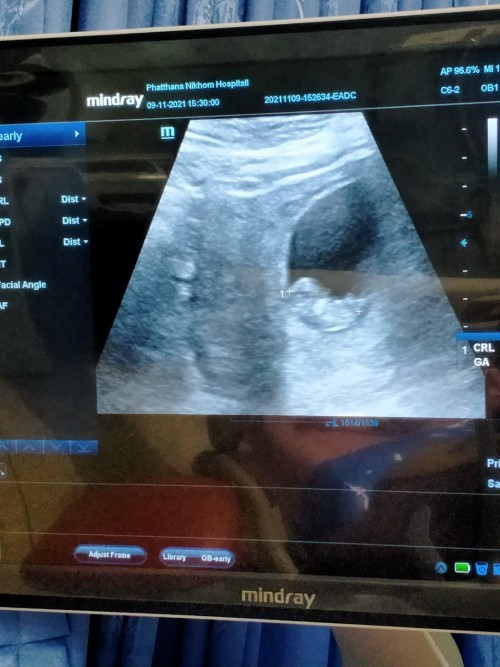

9w ค่ะ ท้องแรก 👶🏻

บ้านนี้ 9+3วิคจร้